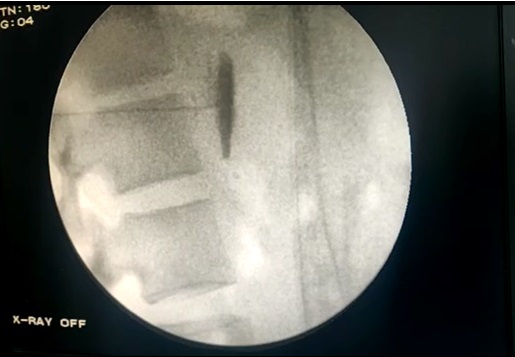

Πρόκειται για ελάχιστα επεμβατικές θεραπείες, οι οποίες εκτελούνται με διαδερμική προσπέλαση και ενδείκνυνται για τη θεραπεία του πόνου σε ασθενείς με οστεοπορωτικά και παθολογικά κατάγματα των σπονδύλων από μεταστατική καρκινική νόσο. Η κυφοπλαστική αποκαθιστά το ύψος του σπονδύλου με χρήση ειδικού μπαλονιού και εισαγωγή τσιμέντου, ενώ η σπονδυλοπλαστική αφορά σε απλή εισαγωγή τσιμέντου στον καταγματικό σπόνδυλο. Και οι δύο τεχνικές γίνονται μέσω ειδικών trocar που εισάγονται διαδερμικά υπό ακτινοσκοπικό έλεγχο στους αυχένες των σπονδύλων και προωθούνται στο σπονδυλικό σώμα, όπου γίνεται η έγχυση του τσιμέντου ταχείας πήξης. Το τσιμέντο σταθεροποιεί τον σπόνδυλο και αποτρέπει την ανάπτυξη κύφωσης στα πάσχοντα σημεία.

Η κυφοπλαστική επιλέγεται για πρόσφατα κατάγματα (έως 6 μηνών). Και οι δύο τεχνικές μπορούν να εφαρμοσθούν σε πολλά επίπεδα της σπονδυλικής στήλης. Έχουν μικρό ποσοστό επιπλοκών και προσφέρουν άμεση ανακούφιση από τον πόνο και ταχεία αποκατάσταση του ασθενούς. Χρειάζονται νοσηλεία μιας μέρας. Σε ασθενείς υψηλού κινδύνου γίνεται να ολοκληρωθούν με μέθη και όχι γενική αναισθησία.